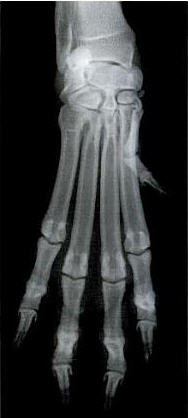

Was fehlt da für ein Eingriff? Richtig - präventive Daumenamputation bei Saugwelpen! Und das in der deutschen GOT?